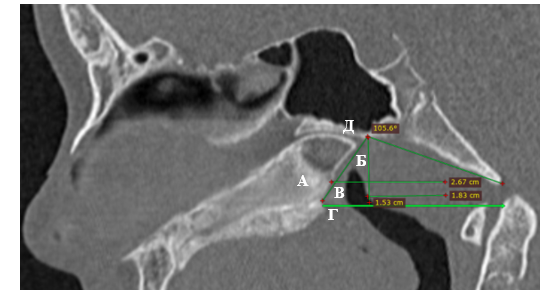

Для определения формы носоглотки использовалось соотношение линейных параметров (длина, ширина, высота) и угла положения свода глотки относительно основания черепа. Длина носоглотки – расстояние от заднего края сошника до задней стенки глотки в сагиттальной проекции; ее ширина – расстояние между наиболее латеральными точками хоан в аксиальной проекции; ее высота – вертикальная линия от основания черепа, перпендикулярная к проекционной линии твердого неба и верхнего края дуги атланта в сагиттальной проекции; угол положения свода глотки относительно основания черепа – между проекционными линиями, проходящими через наружную поверхность ската затылочной кости и задний край сошника в сагиттальной проекции (рис.1, 2).

Рис.1. Линейные параметры носоглотки и глоточной миндалины на КТ головы девочки 13 лет в сагиттальной проекции: А – длина носоглотки; Б – высота носоглотки и высота глоточной миндалины в данном случае совпадают; В – длина глоточной миндалины; Г – проекционная линия; Д – угол положения свода глотки.

Примечание: составлен авторами по результатам данного исследования